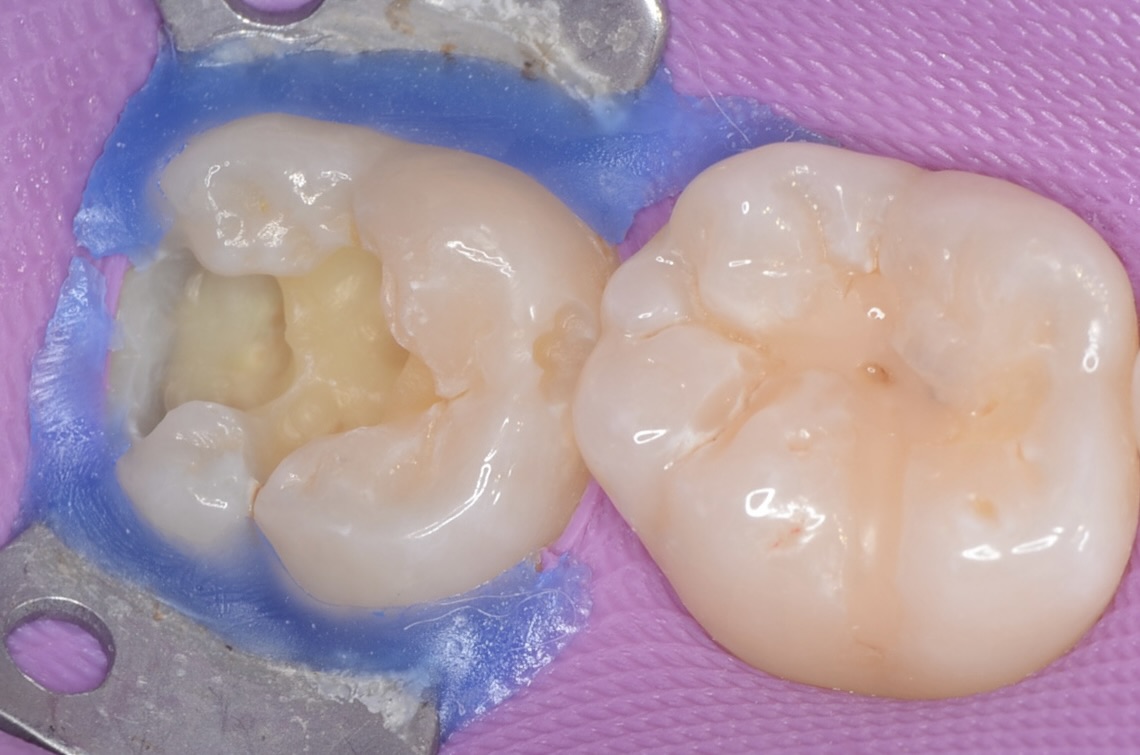

虫歯除去

青い齲蝕検知液で虫歯を染めて染まった部分を削ります。この工程を青く染まらなくなるまで歯にできるだけダメージがないように優しい力で丁寧に行います。この作業は時間がかかります。保険診療の短い時間で行うことは限界があります。 -

側面の虫歯

細い器具で触ったところ、粘りつくような感覚がありました。中で虫歯が広がっているようです。 -

少しだけエナメル質を削ったところ

内部に虫歯が広がっているのを確認できました。 -

虫歯を完全に削りました。小さな穴に見えても、虫歯は歯の中で広がっていることが多いです。 -